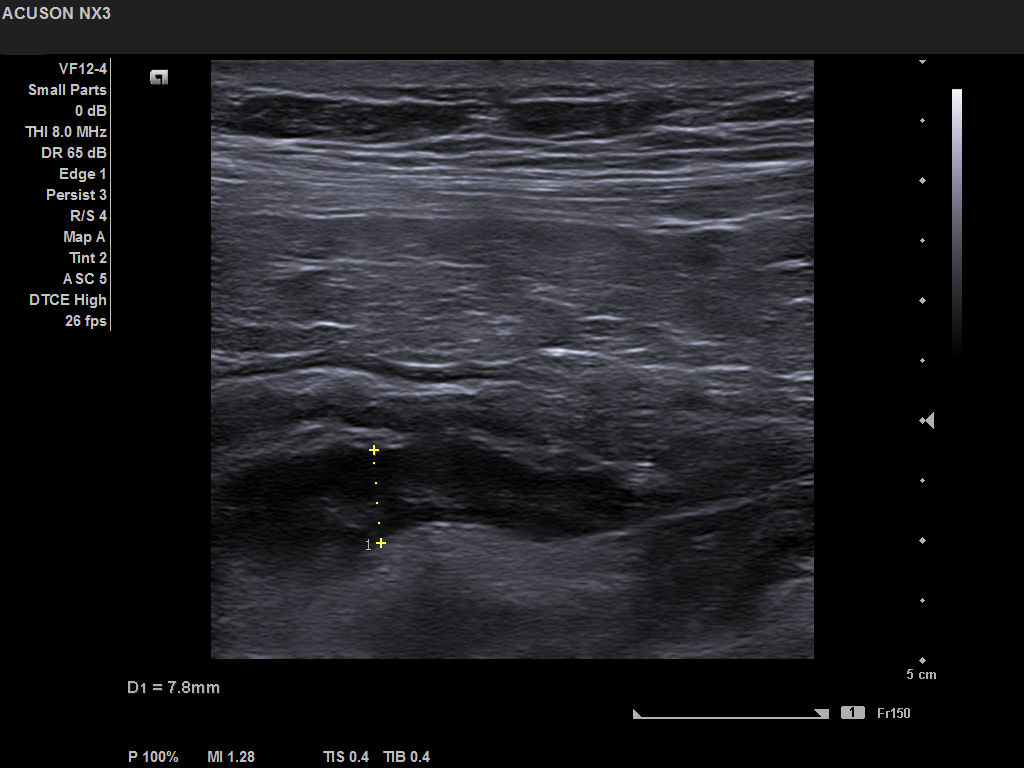

Student Image Challenge 68October 8, 2020Student Image Challenge 70October 22, 2020 Student Image Challenge 69 Student Image Challenge #69 1 / 1 Student Image Challenge #69 A 56-year-old man with four days of right lower quadrant pain and nausea, presents to the gastroenterology clinic. At examination a palpable mass was found. The ultrasound examination revealed this aspect. What is your diagnosis? Perforated appendix Appendiceal phlegmon Appendiceal diverticulitis Appendiceal lymphoma Appendiceal adenocarcinoma Incorrect ....Please see the correct answer highlighted Correct: Appendiceal phlegmon Your score isThe average score is 100% LinkedIn Facebook VKontakte 0% Restart quiz Case courtesy of Sevastița Iordache MD EFSUMBAdmin Related postsStudent Image Challenge 111Read more Comments are closed.